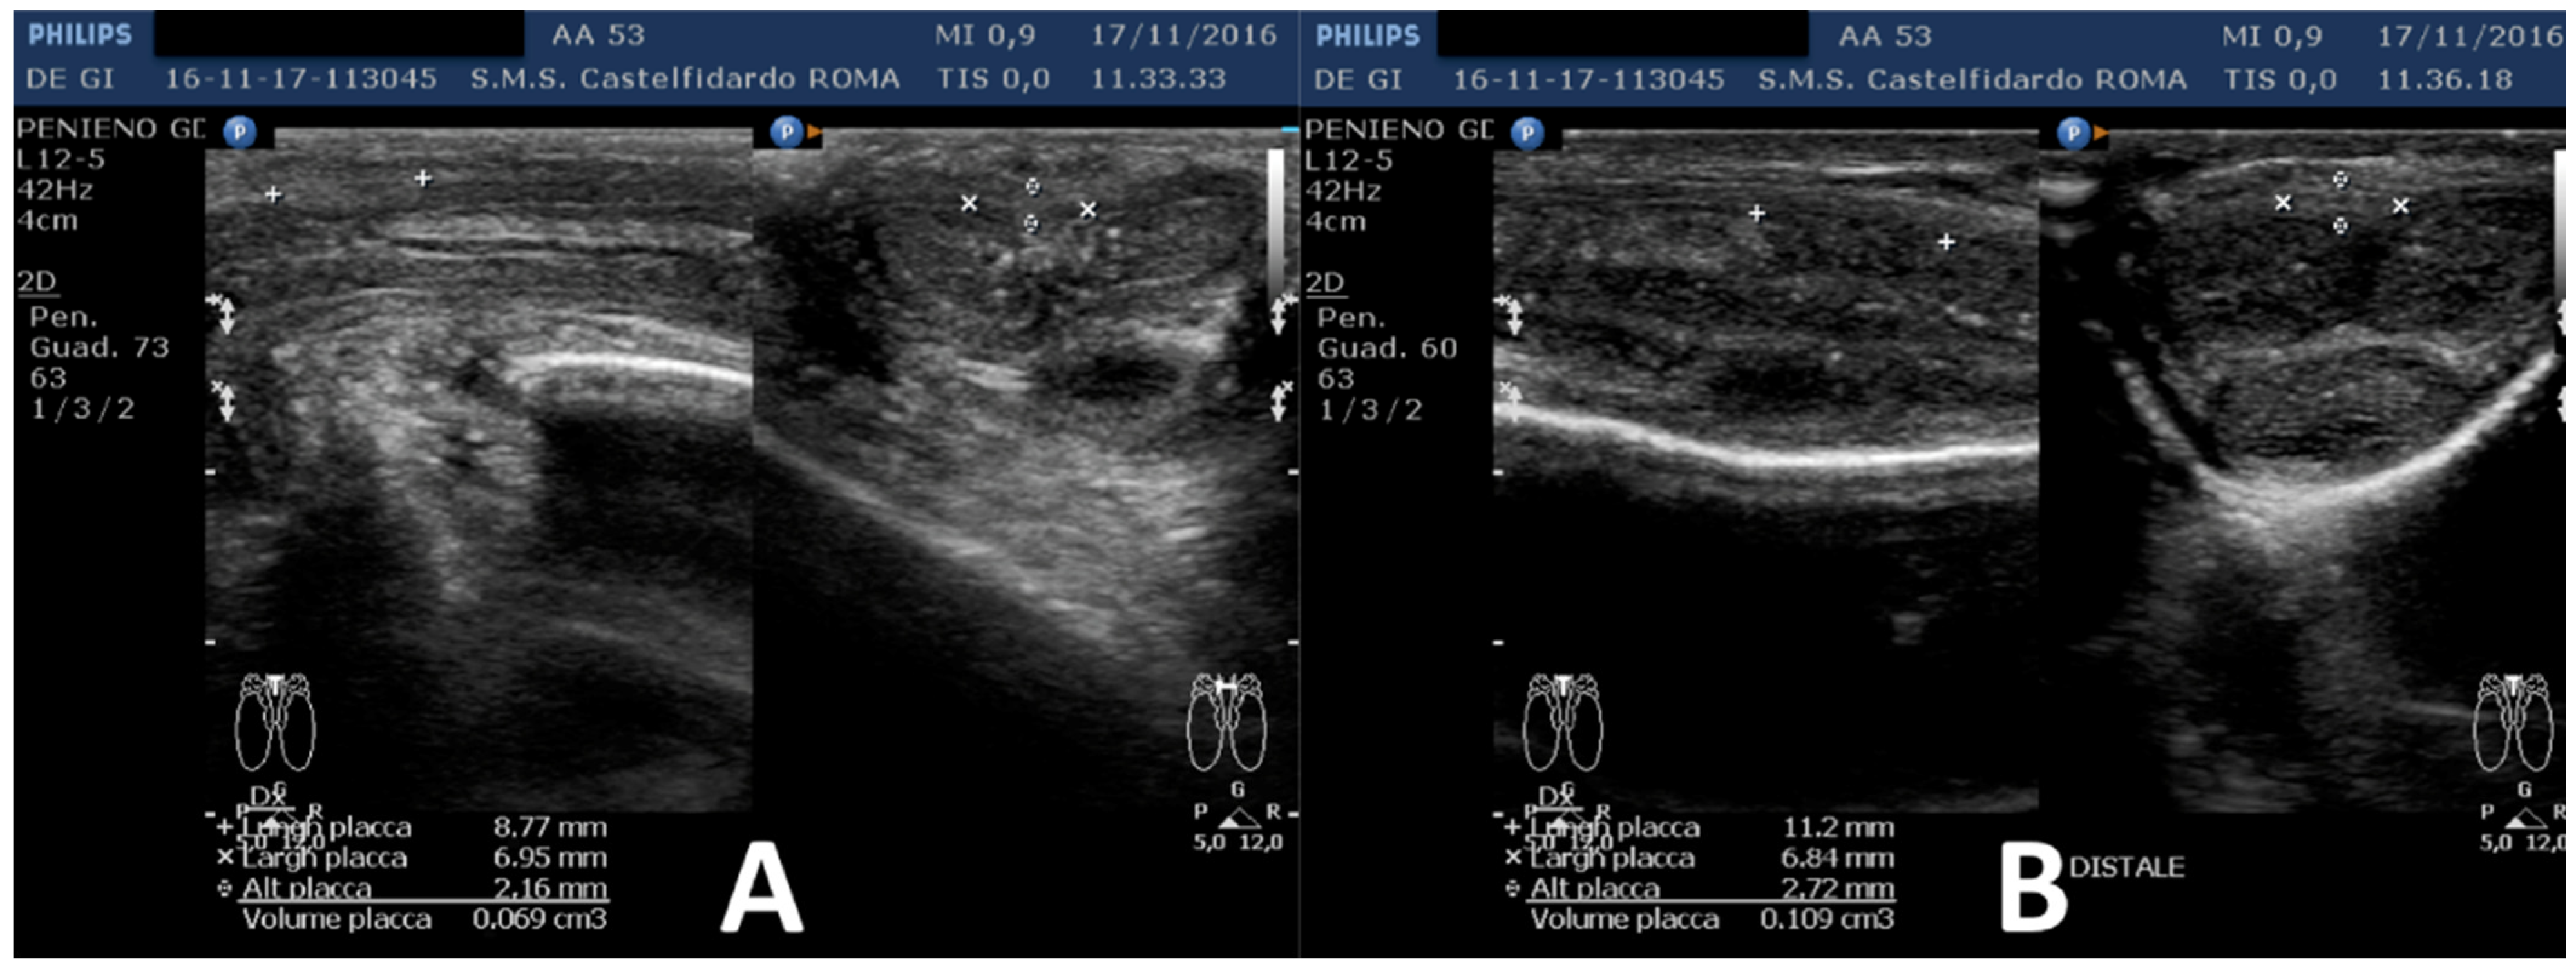

| No. | Patient Age | Associated Disease | Penile Plaque Site | Ultrasound Measurements (Length × Width × Thickness) and Plaque Volume before (A) and after Treatment (B) | Type of Deformity Initial (A) and after Treatment (B) | Pain Score/VAS Scale (1–10) | IIEF Score before and after Treatment | Total Duration of Treatment until Plaque Regression | Complete Combined Multimodal Treatment |

|---|---|---|---|---|---|---|---|---|---|

| 1 | 31 years | Chronic prostatitis and associated anxious and depressive state. | Distal third | (A) 15.1 × 12.1 × 3.7 mm volume = 353 mm3 (B) No plaque detected | (A) 10-degree ventral curvature + 15-degree left curvature (B) None | VAS score = 8 Pain disappeared after 12 months | 26 > 27 | 30 months | Orally: propolis 600 mg + bilberry 160 mg + silymarin 400 mg + ginkgo biloba 250 mg + L-carnitine 1000 mg + coenzyme Q10 100 mg + Boswellia 200 mg + Vitamin E 30 mg/daily/for 30 months + topically: diclofenac gel 4%/2× daily for 30 months Note: The patient refused periplaque penile injections with pentoxifylline |

| 2 | 52 years | Dupuytren’s disease, Ledderhose disease, congenital dorsal penile curvature (5 degrees). | Middle third + distal third | (A) First plaque: 13.4 × 9.15 × 2.83 mm volume = 182 mm3. Second plaque: 14.8 × 8.43 × 3.87 mm. Total volume = 252 mm3 (B) No plaque detected | (A) 20-degree dorsal penile curvature + 20-degree left penile curvature (B) 5-degree dorsal penile curvature. Previous condition = congenital dorsal penile curvature (5 degrees) | VAS score = 0 | 26 > 27 | 51 months | Orally: propolis 600 mg + bilberry 160 mg + silymarin 400 mg + ginkgo biloba 250 mg + L-carnitine 1000 mg + coenzyme Q10 100 mg + Boswellia 200 mg + vitamin E 30 mg/daily for 51 months + topically: diclofenac gel 4%/2× daily for 51 months + periplaque penile injections: pentoxifylline 100 mg (30 G needle) every 2 weeks for 6 months, and then 1 penile injection every month for 12 months, and 1 penile injection every 2 months for 24 months (42 total injections) |